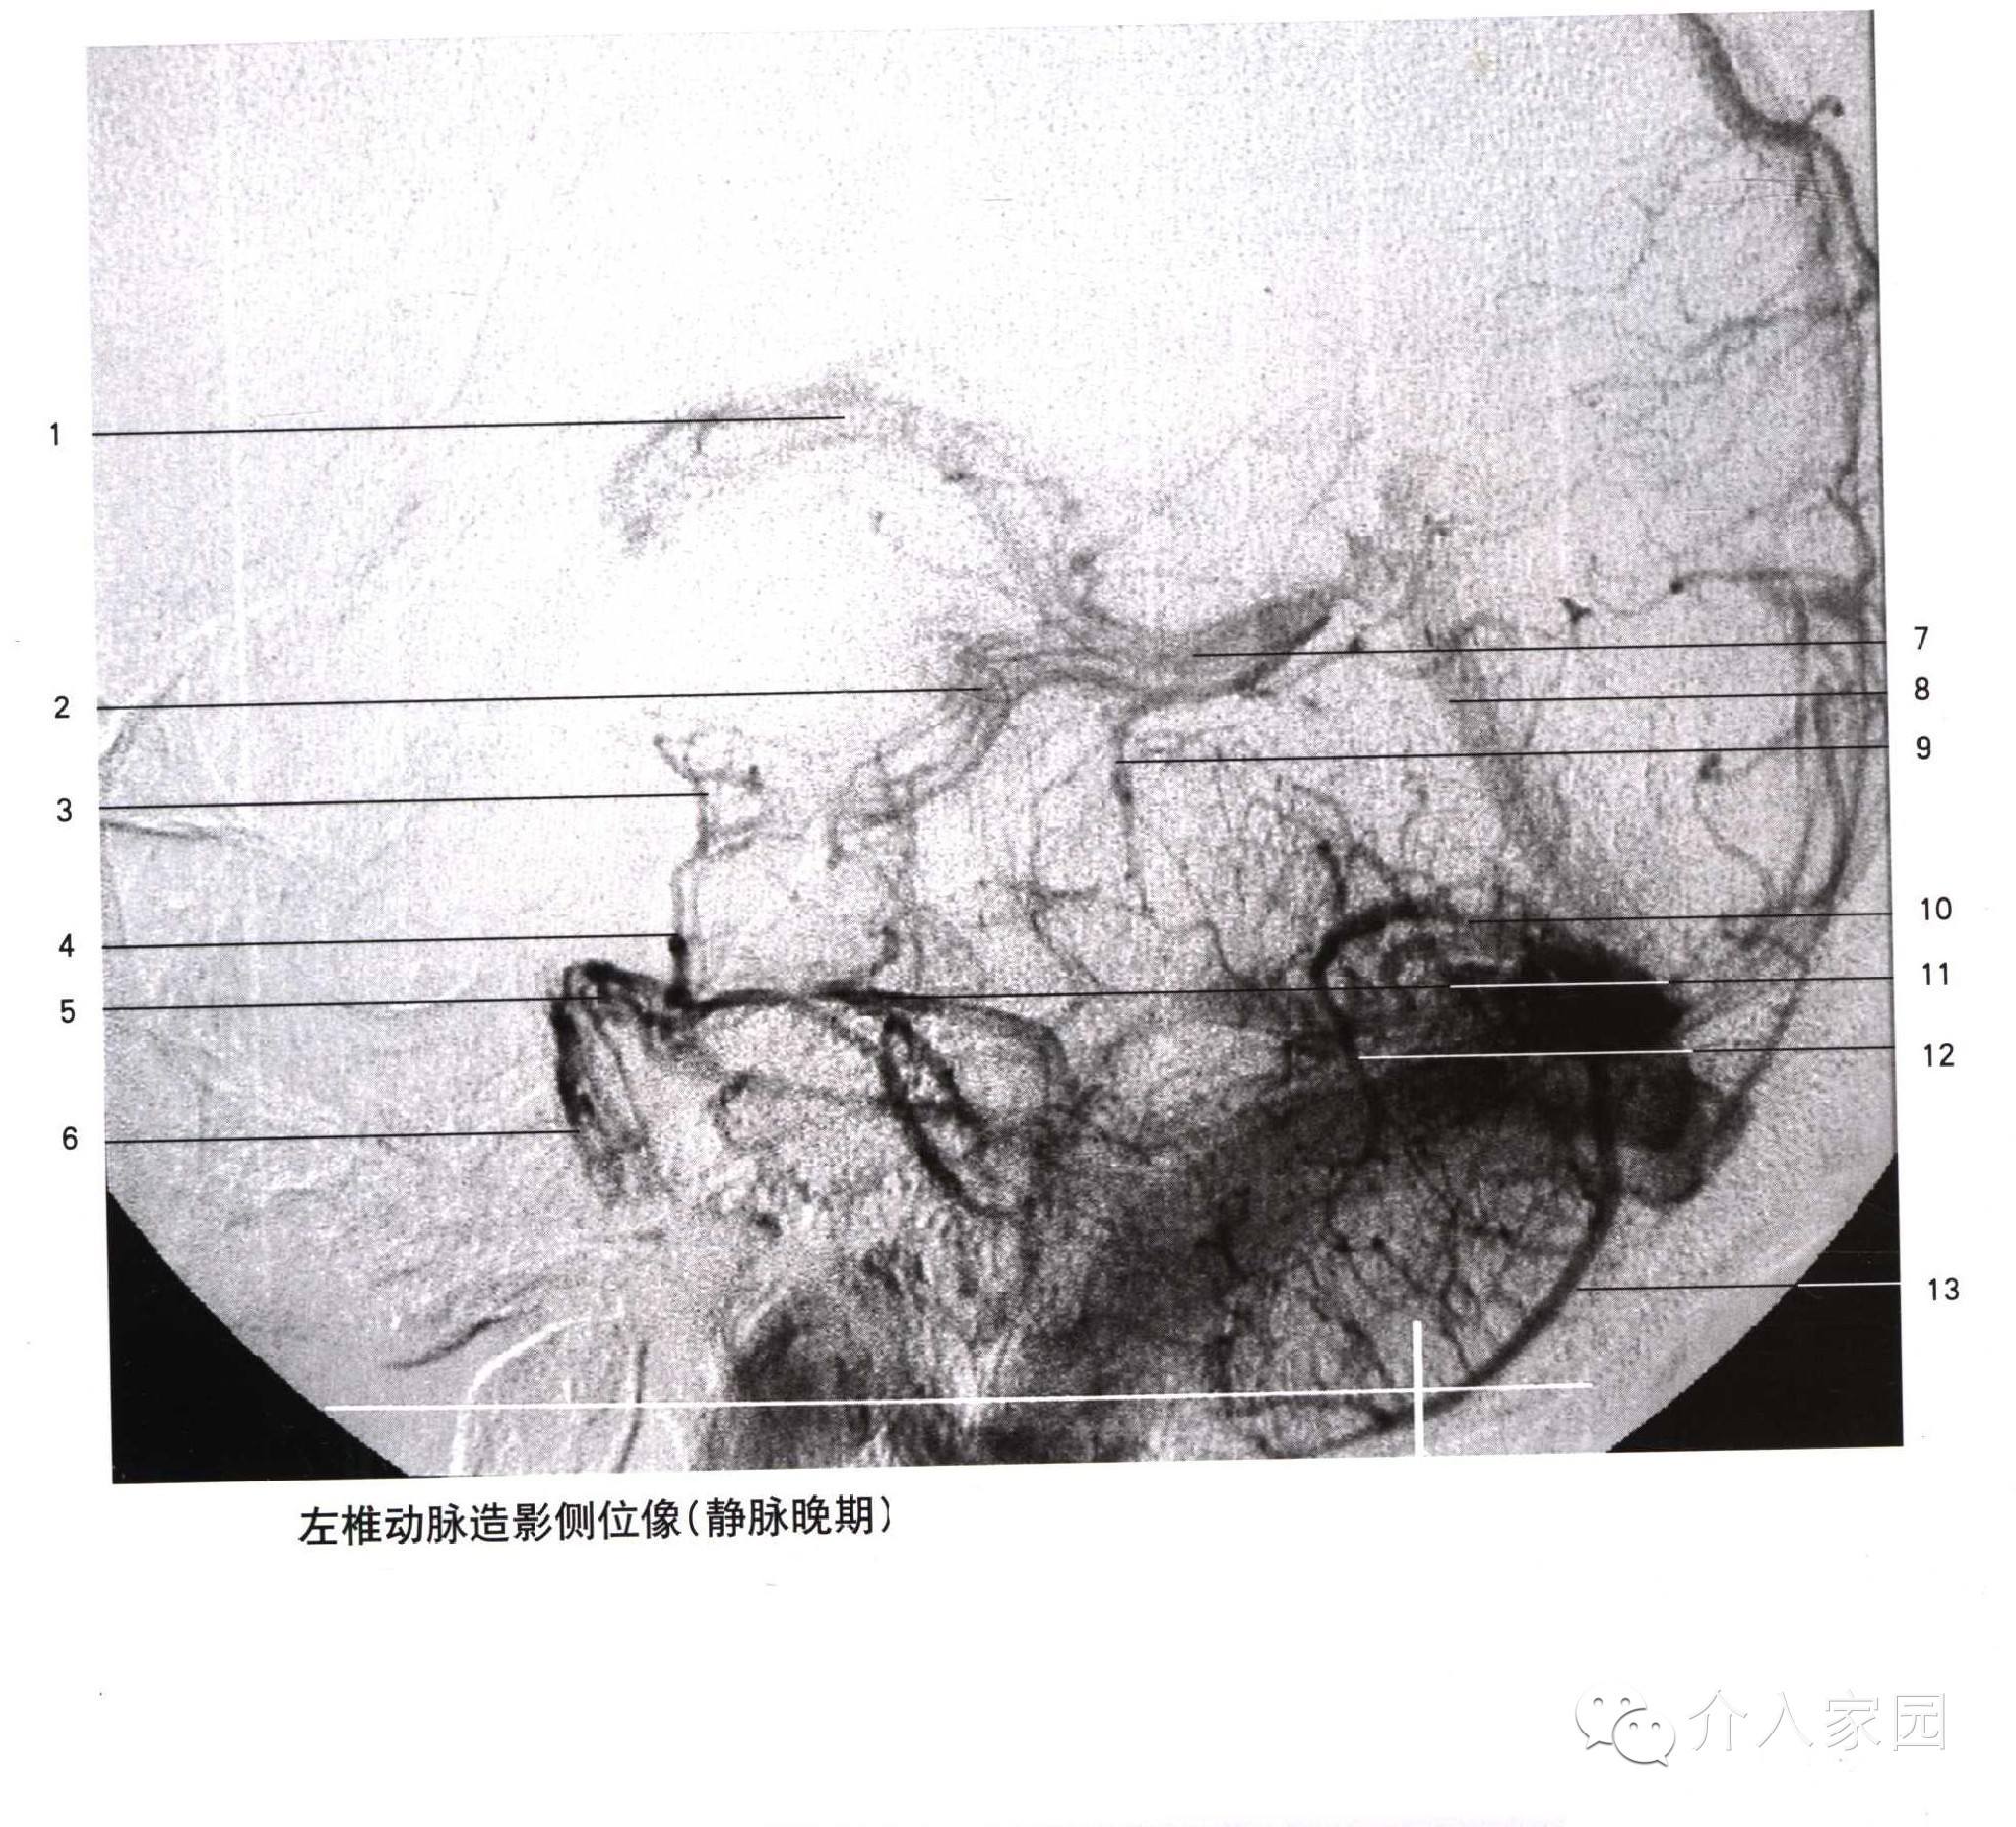

1、上吻合靜脈 2、額升靜脈 3、靜脈角 4、透明隔靜脈 5、大腦中淺靜脈 6、海綿竇 7、岩下竇 8、乙狀竇 9、中央溝靜脈 10、上矢狀竇

11、頂升靜脈 12、下矢狀竇 13、丘紋靜脈 14、胼周後靜脈 15、大腦內靜脈 16、枕升靜脈 17、大腦大靜脈 18、側腦室下靜脈 19、基底靜脈

20、直竇 21、大腦下靜脈 22、竇彙 23、橫竇